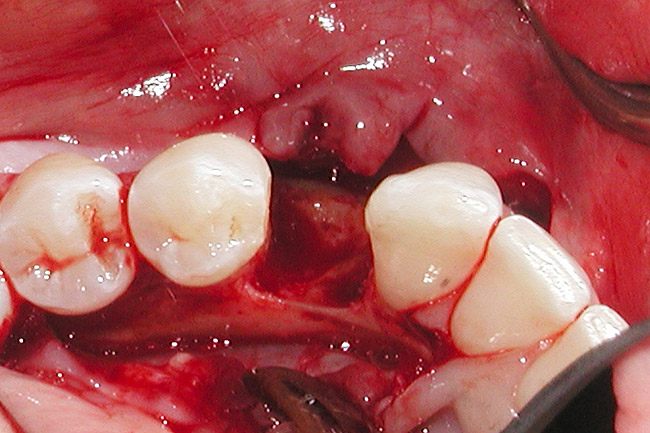

Figure 4  Vertical ridge defect in site No. 22.

Figure 4

Figure 5  Horizontal ridge defect in site No. 22.

Figure 5

The patient had no medical concerns and had a history of an implant placement in December 2002 when she was 25 years old. In February 2005, she presented with a mobile implant and an associated advanced peri-implantitis. Radiographic review at the initial examination demonstrated significant destruction of the dentoalveolar ridge around the implant as well as around the adjacent natural dentition. Emergency-based treatment involved surgical implant removal only and debridement of the infection (Figure 4 and Figure 5). Following uneventful healing, an advanced ridge defect was apparent at the edentulous site and moderate and advanced attachment loss noted at No. 22D and No. 21M, respectively (Figure 6 and Figure 7). This case demonstrates bone loss of two separate origins: lack of bone because of tooth agenesis and destruction of bone from inflammatory peri-implantitis.